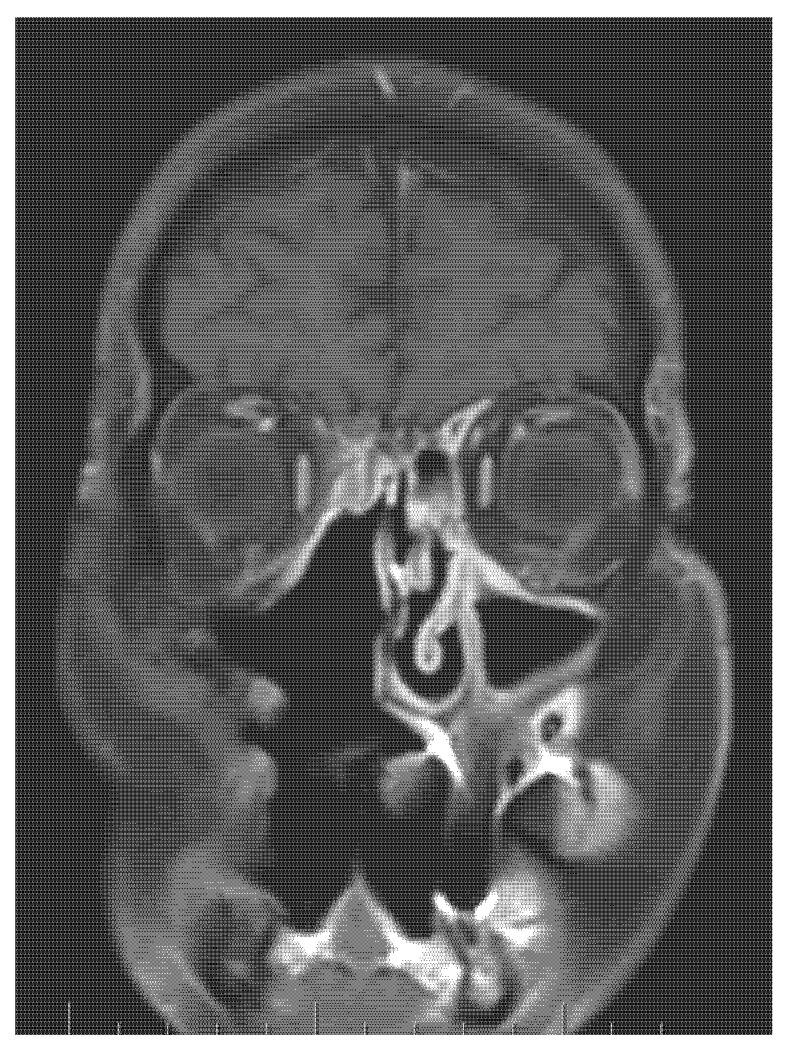

Sarcomas in the head and neck area are rare diseases with an incidence of under 1% of all head and neck malignant tumours. Osteosarcomas or osteogenic sarcomas consist of neoplastic cells that produce osteoid bone or immature bone. Sarcomas develop more in the mandible than the maxilla. The exact diagnosis of different types of sarcomas is based on the immunohistochemical investigation. These rare tumours are of mesenchymal origin; osteosarcomas and chondrosarcomas are the most common types-Ewing's sarcomas. The use of proton beam radiotherapy in the treatment of osteosarcoma of the maxilla is rarely reported in the literature. We present a case of successfully treated (surgery and proton beam radiotherapy) poorly differentiated highly aggressive osteosarcoma in the ethmoids and maxillary sinus and morbidity after the treatment. We were presented with a case of a 65-year-old man with anaesthesia and palsy of the right face. The stomatology department performed the extraction of a tooth. One month later, the wound was still open. The histology showed an osteogenic sarcoma in the area of the wound. The oncologist and maxillofacial surgeons in a catchment hospital recommended a nonsurgical approach. Hence, we performed a radical maxillectomy and ethmoidectomy, after which we continued with proton bean radiotherapy. The patient is now five years after therapy without signs of sarcoma; however, he has blindness in the right eye and reduced vision in the left eye, as well as gliosis of the brain, vertigo, tinnitus, trismus, and ancylostomiases. Head and neck osteosarcomas treatment is considered a complex multidisciplinary task. It is currently argued that there is no clear therapeutic protocol for successful treatment. Innovations in treatment modalities such as proton beam radiotherapy appear to have potential, although their effects on long-term morbidity and survival outcomes are still undetermined. We present a rare case report of an osteosarcoma of the maxilla involving an innovative, successful treatment procedure combining surgical excision followed by proton beam radiotherapy. This treatment approach may enable maximum tumour control. This protocol has not been adequately described in the world literature for this diagnosis.

头颈部肉瘤是一种罕见疾病,发病率低于所有头颈部恶性肿瘤的 1%。骨肉瘤或成骨肉瘤由产生骨样骨或未成熟骨的肿瘤细胞组成。肉瘤在下颌骨比上颌骨更常见。不同类型肉瘤的准确诊断基于免疫组织化学研究。这些罕见的肿瘤来源于间充质;骨肉瘤和软骨肉瘤是最常见的类型——尤因肉瘤。质子束放疗在治疗上颌骨骨肉瘤中的应用在文献中很少报道。我们报告了一例成功治疗(手术和质子束放疗)的筛窦和上颌窦未分化高度侵袭性骨肉瘤病例,以及治疗后的发病率。我们报告了一例 65 岁男性,出现右侧面部麻醉和瘫痪。口腔科进行了拔牙。一个月后,伤口仍未愈合。组织学显示伤口处有骨肉瘤。收治医院的肿瘤学家和颌面外科医生建议采用非手术方法。因此,我们进行了根治性上颌骨切除术和筛窦切除术,之后继续进行质子束放疗。患者在治疗后五年无肉瘤迹象,但右眼失明,左眼视力下降,同时伴有脑胶质增生、眩晕、耳鸣、牙关紧闭和Ancylostomiases。头颈部骨肉瘤的治疗被认为是一项复杂的多学科任务。目前认为,对于成功治疗,尚无明确的治疗方案。治疗方式的创新,如质子束放疗,似乎具有潜力,尽管其对长期发病率和生存结果的影响仍不确定。我们报告了一例罕见的上颌骨肉瘤病例,采用了一种创新的、成功的治疗方法,结合了手术切除和质子束放疗。这种治疗方法可能能够最大限度地控制肿瘤。这种方案在世界范围内针对这一诊断的文献中尚未得到充分描述。